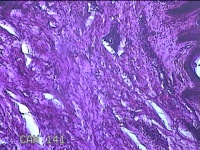

前胸部包块

性别

女

年龄

45岁

临床诊断

皮脂腺囊肿

一般病史

发现前胸部包块3个月余。

标本名称

大体所见

灰白暗红色组织2.2x1x0.8cm一块,表面带梭形皮肤2.2x1.3cm,皮下见包块1.8x1.2x0.8一块,切开包块呈实性,切面灰白粉红色,质软。